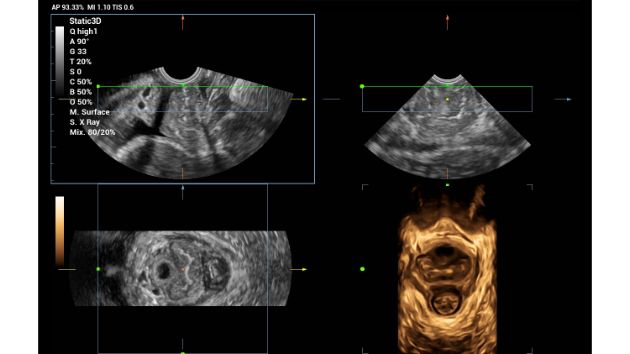

Smart OB/NT

Realizing the increasing importance of ultrasound diagnosis on pelvic floor disorders, Smart Pelvic provides a new solution to greatly simplify the operation procedures, and to minimize the exam time for a standardized evaluation on pelvic floor. With extremely simple user-interaction, it generates a standard coordinate system and automatically provides related measurements within a few seconds.

Consona Series Women Health Solution - Smart Pelvic feature image

Smart Pelvic 3D